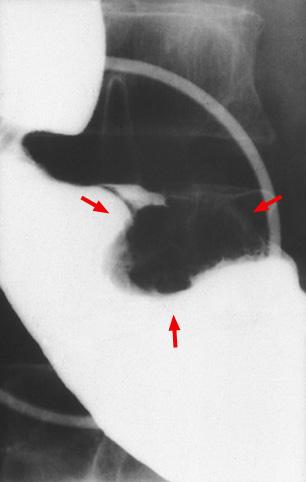

疾病(病理主体)的分类恶性上皮性肿瘤/腺癌

部位(按器官分)胃(部位)/前庭

检查方法X线

肿瘤的肉眼分类1型(肿瘤型)/

肿瘤最大直径25~29

肿瘤的深度s(a)